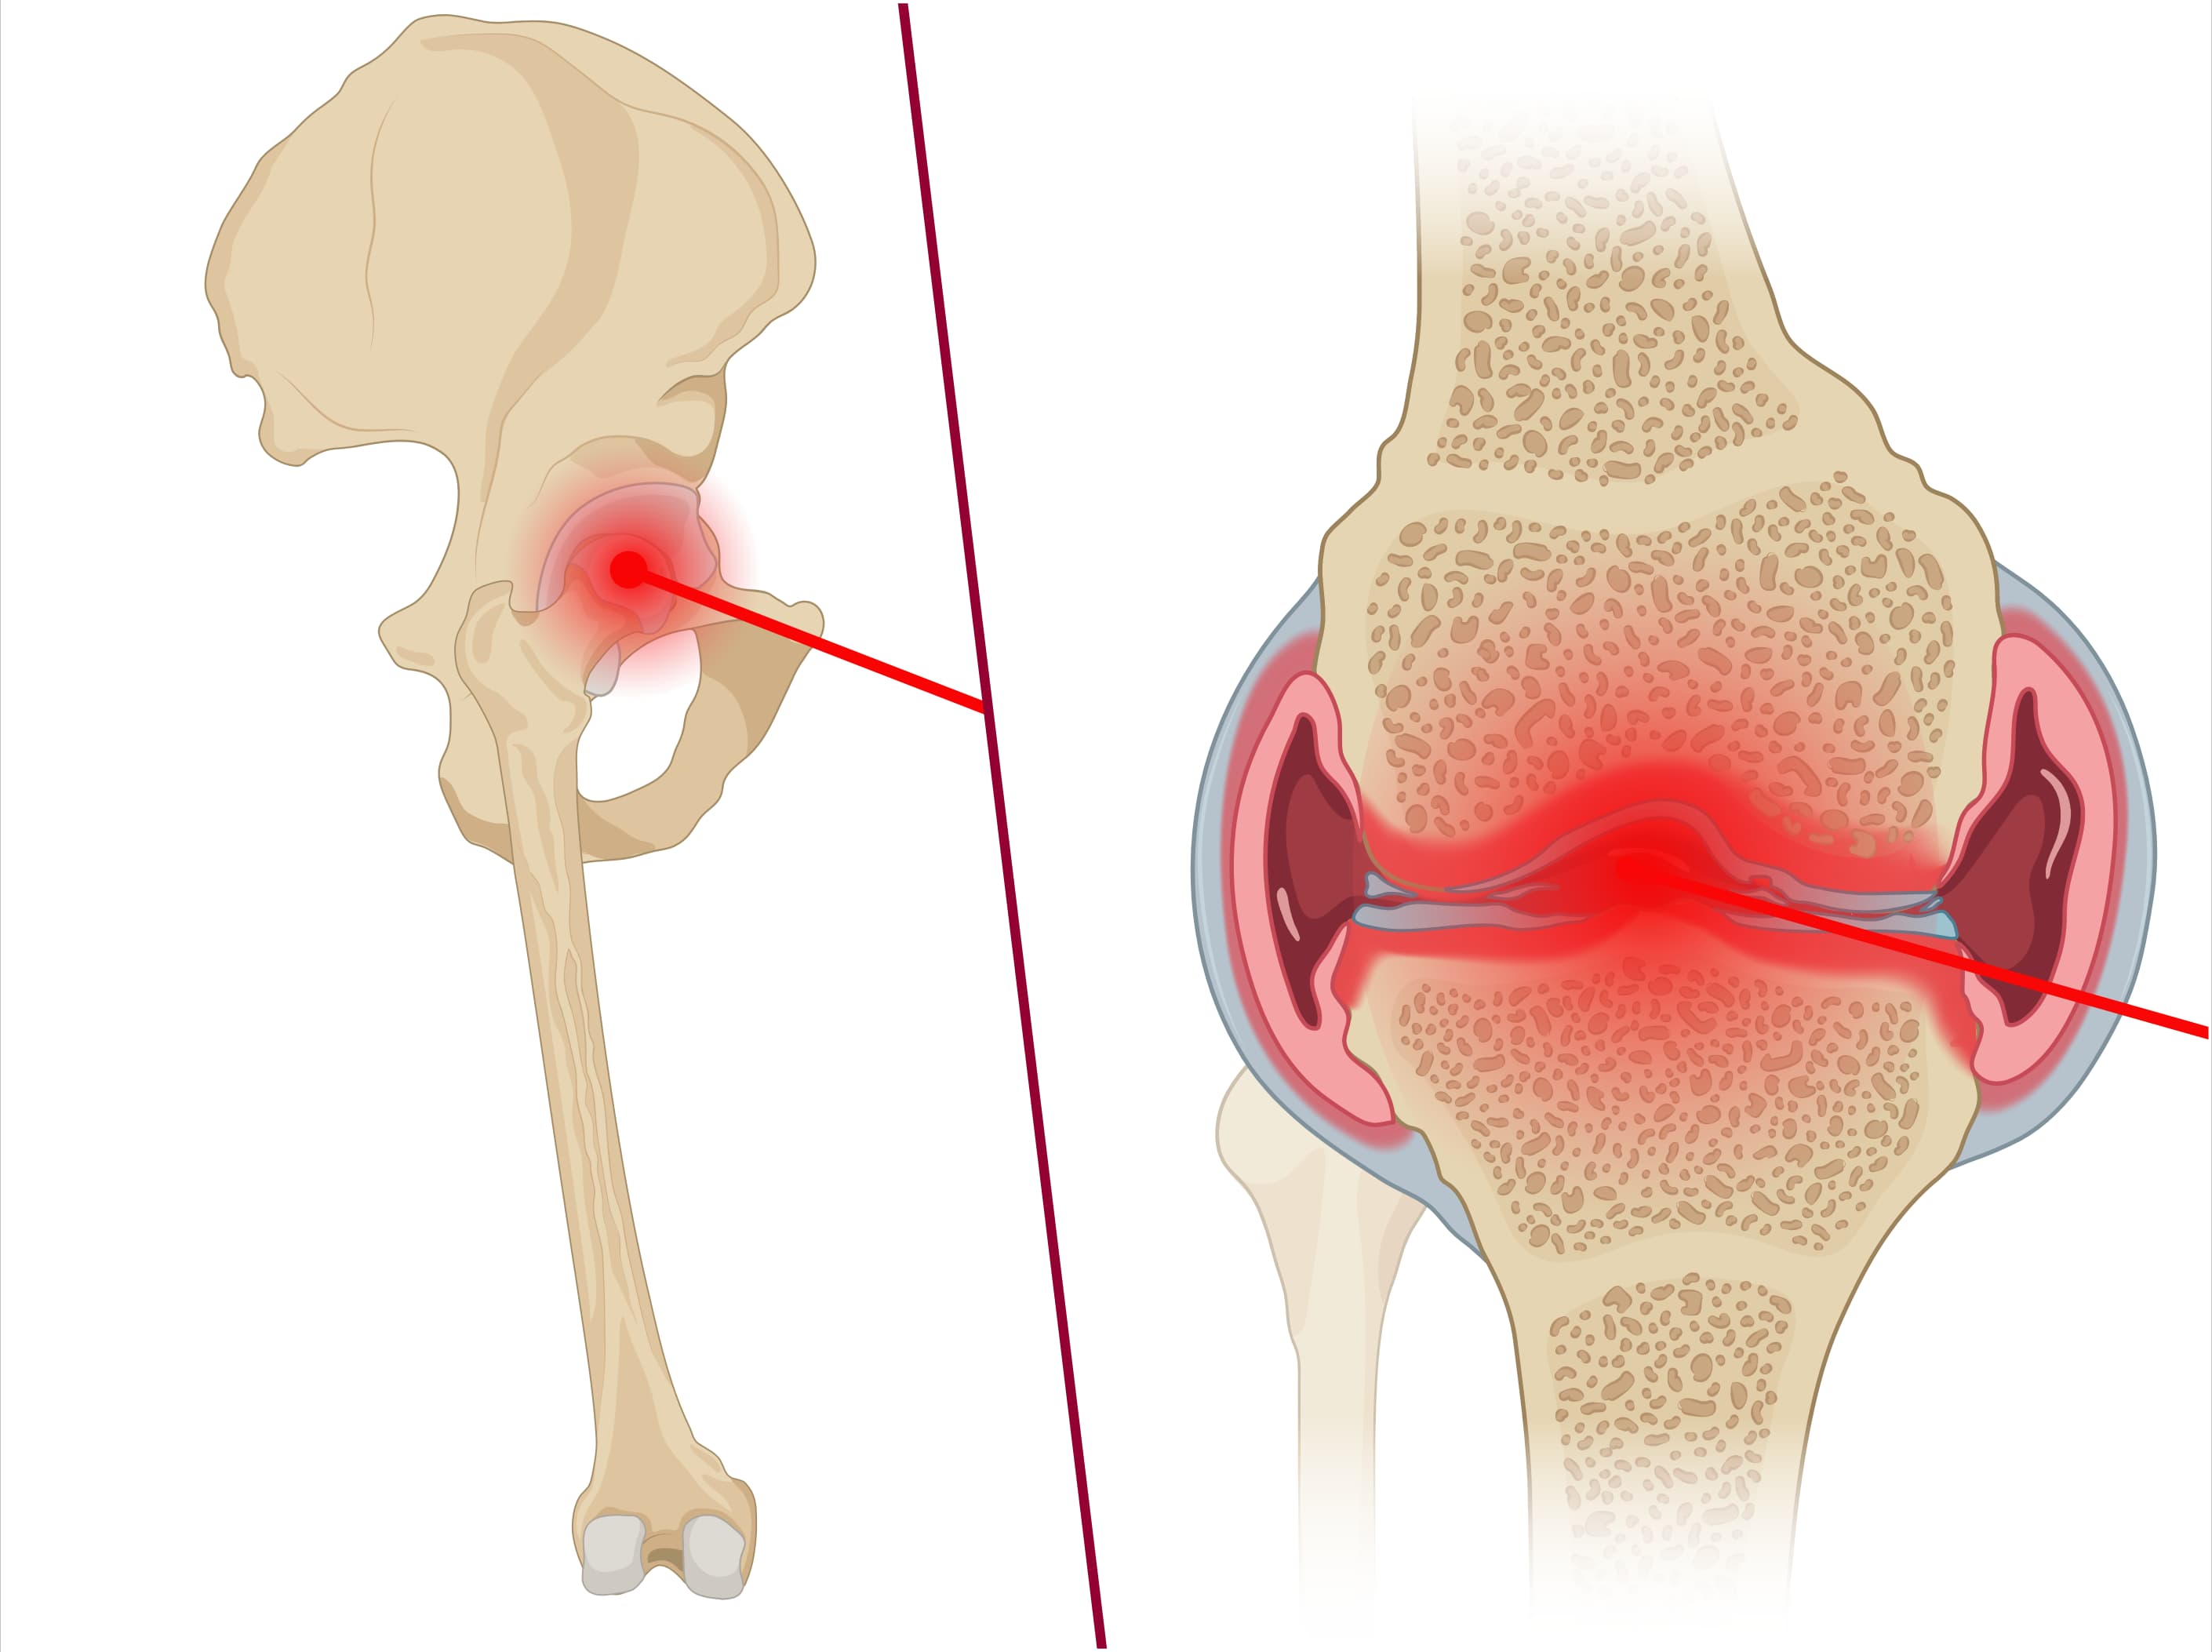

Septic arthritis

Prediction of septic arthritis.

Explore our collection of statistical models designed to predict the probability of septic hip arthritis or septic knee arthritis.